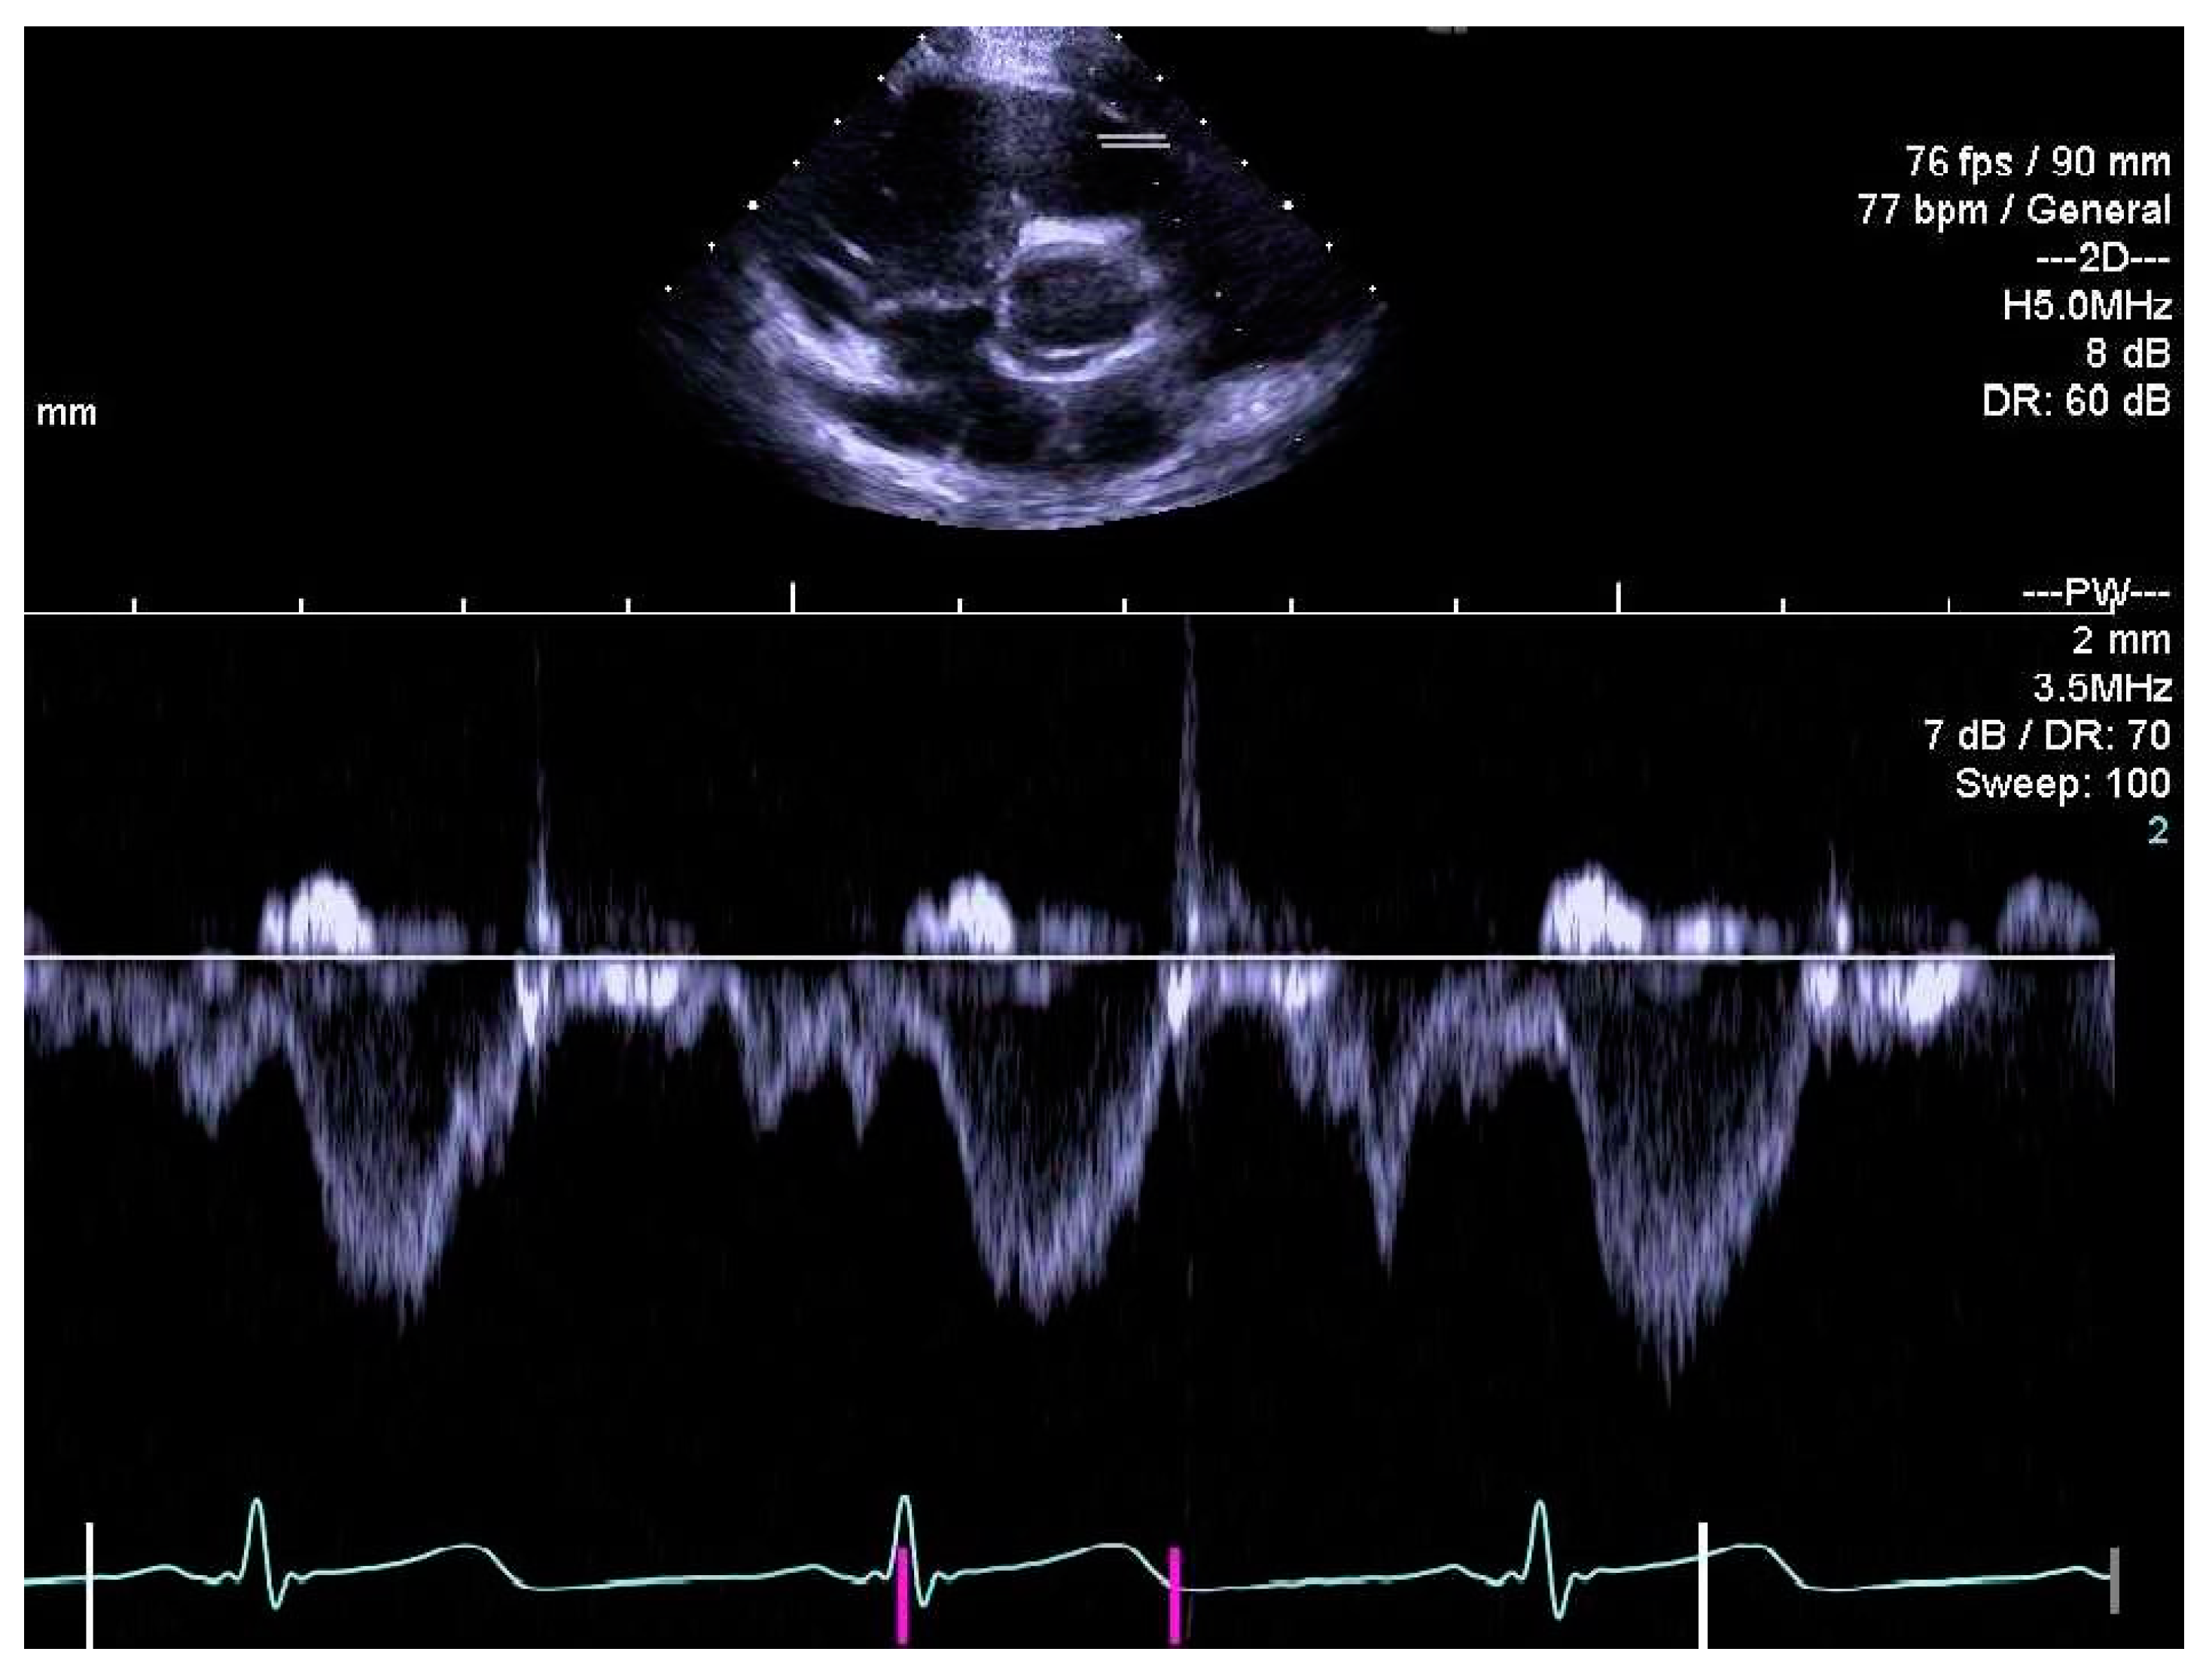

2.4. Determination of Right Heart Outcome Variables

3.5. Right Heart Systolic and Diastolic Functions

3.6. Perinatal Risk Factors and Right Heart Structure and Function in Children Born Extremely Preterm